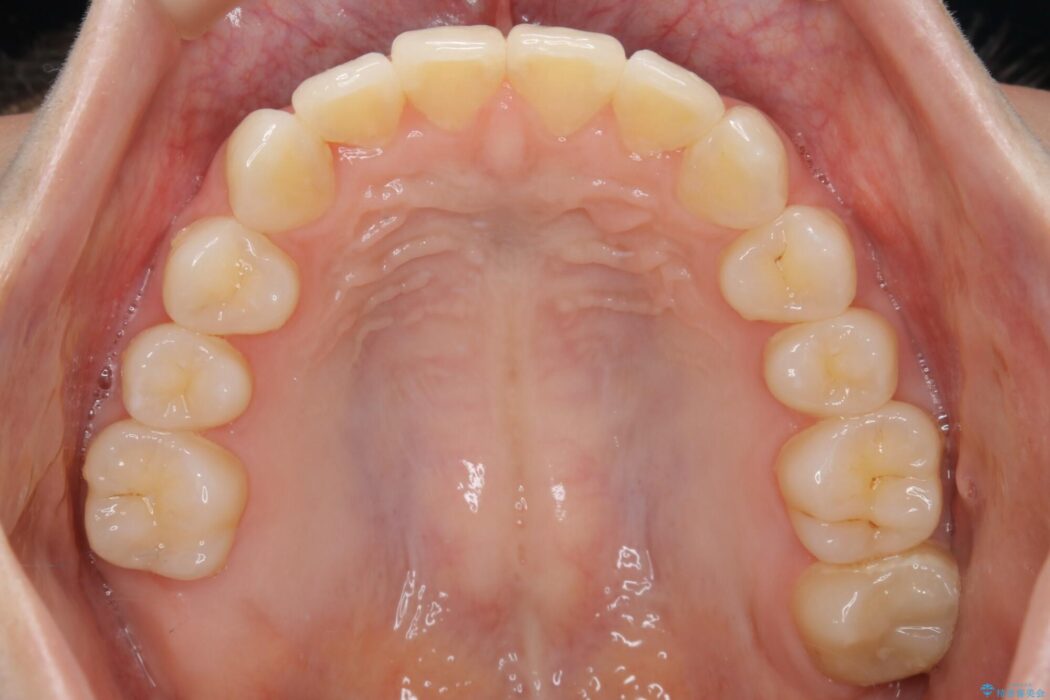

【20代女性】ブライダルに向けた矯正できれいなスマイルラインへ

- 患者様:20代女性

- 治療期間:1年10ヶ月

- 矯正装置:インビザライン コンプリヘンシブパッケージ

笑った時に見える歯並びをきれいにしたいとの主訴で来院されました。

ガタつきの度合いから抜歯は不要と判断しましたので、マイクロインプラントを用いて歯全体を遠心移動させていくことでねじれや噛み合わせのズレを改善していく計画を立てました。